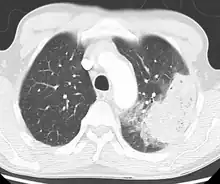

| Chest X-ray of a pneumonia caused by influenza and Haemophilus influenzae, with patchy consolidations, mainly in the right upper lobe (arrow) | |